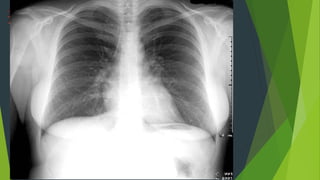

1. Hoàn toàn thẳng: bờ trong xương đòn đối xứng nhau qua

đường giữa Cân xứng : mức hơi dịch ở túi hơi dạ dày, hai

xương bả vai tách ra khỏi lồng ngực.

2. Hít vào đủ sâu: cung trước xương sườn 6 - 7 trên vòm

hoành. Cung sau ở xương sườn 10 trở xuống

3. Độ đối quang tốt : Thấy được 3 - 4 đốt sống ngực

trên,thấy được mạch máu sau tim gan, thấy mạch máu

cách ngoại vi phổi 1-2cm.